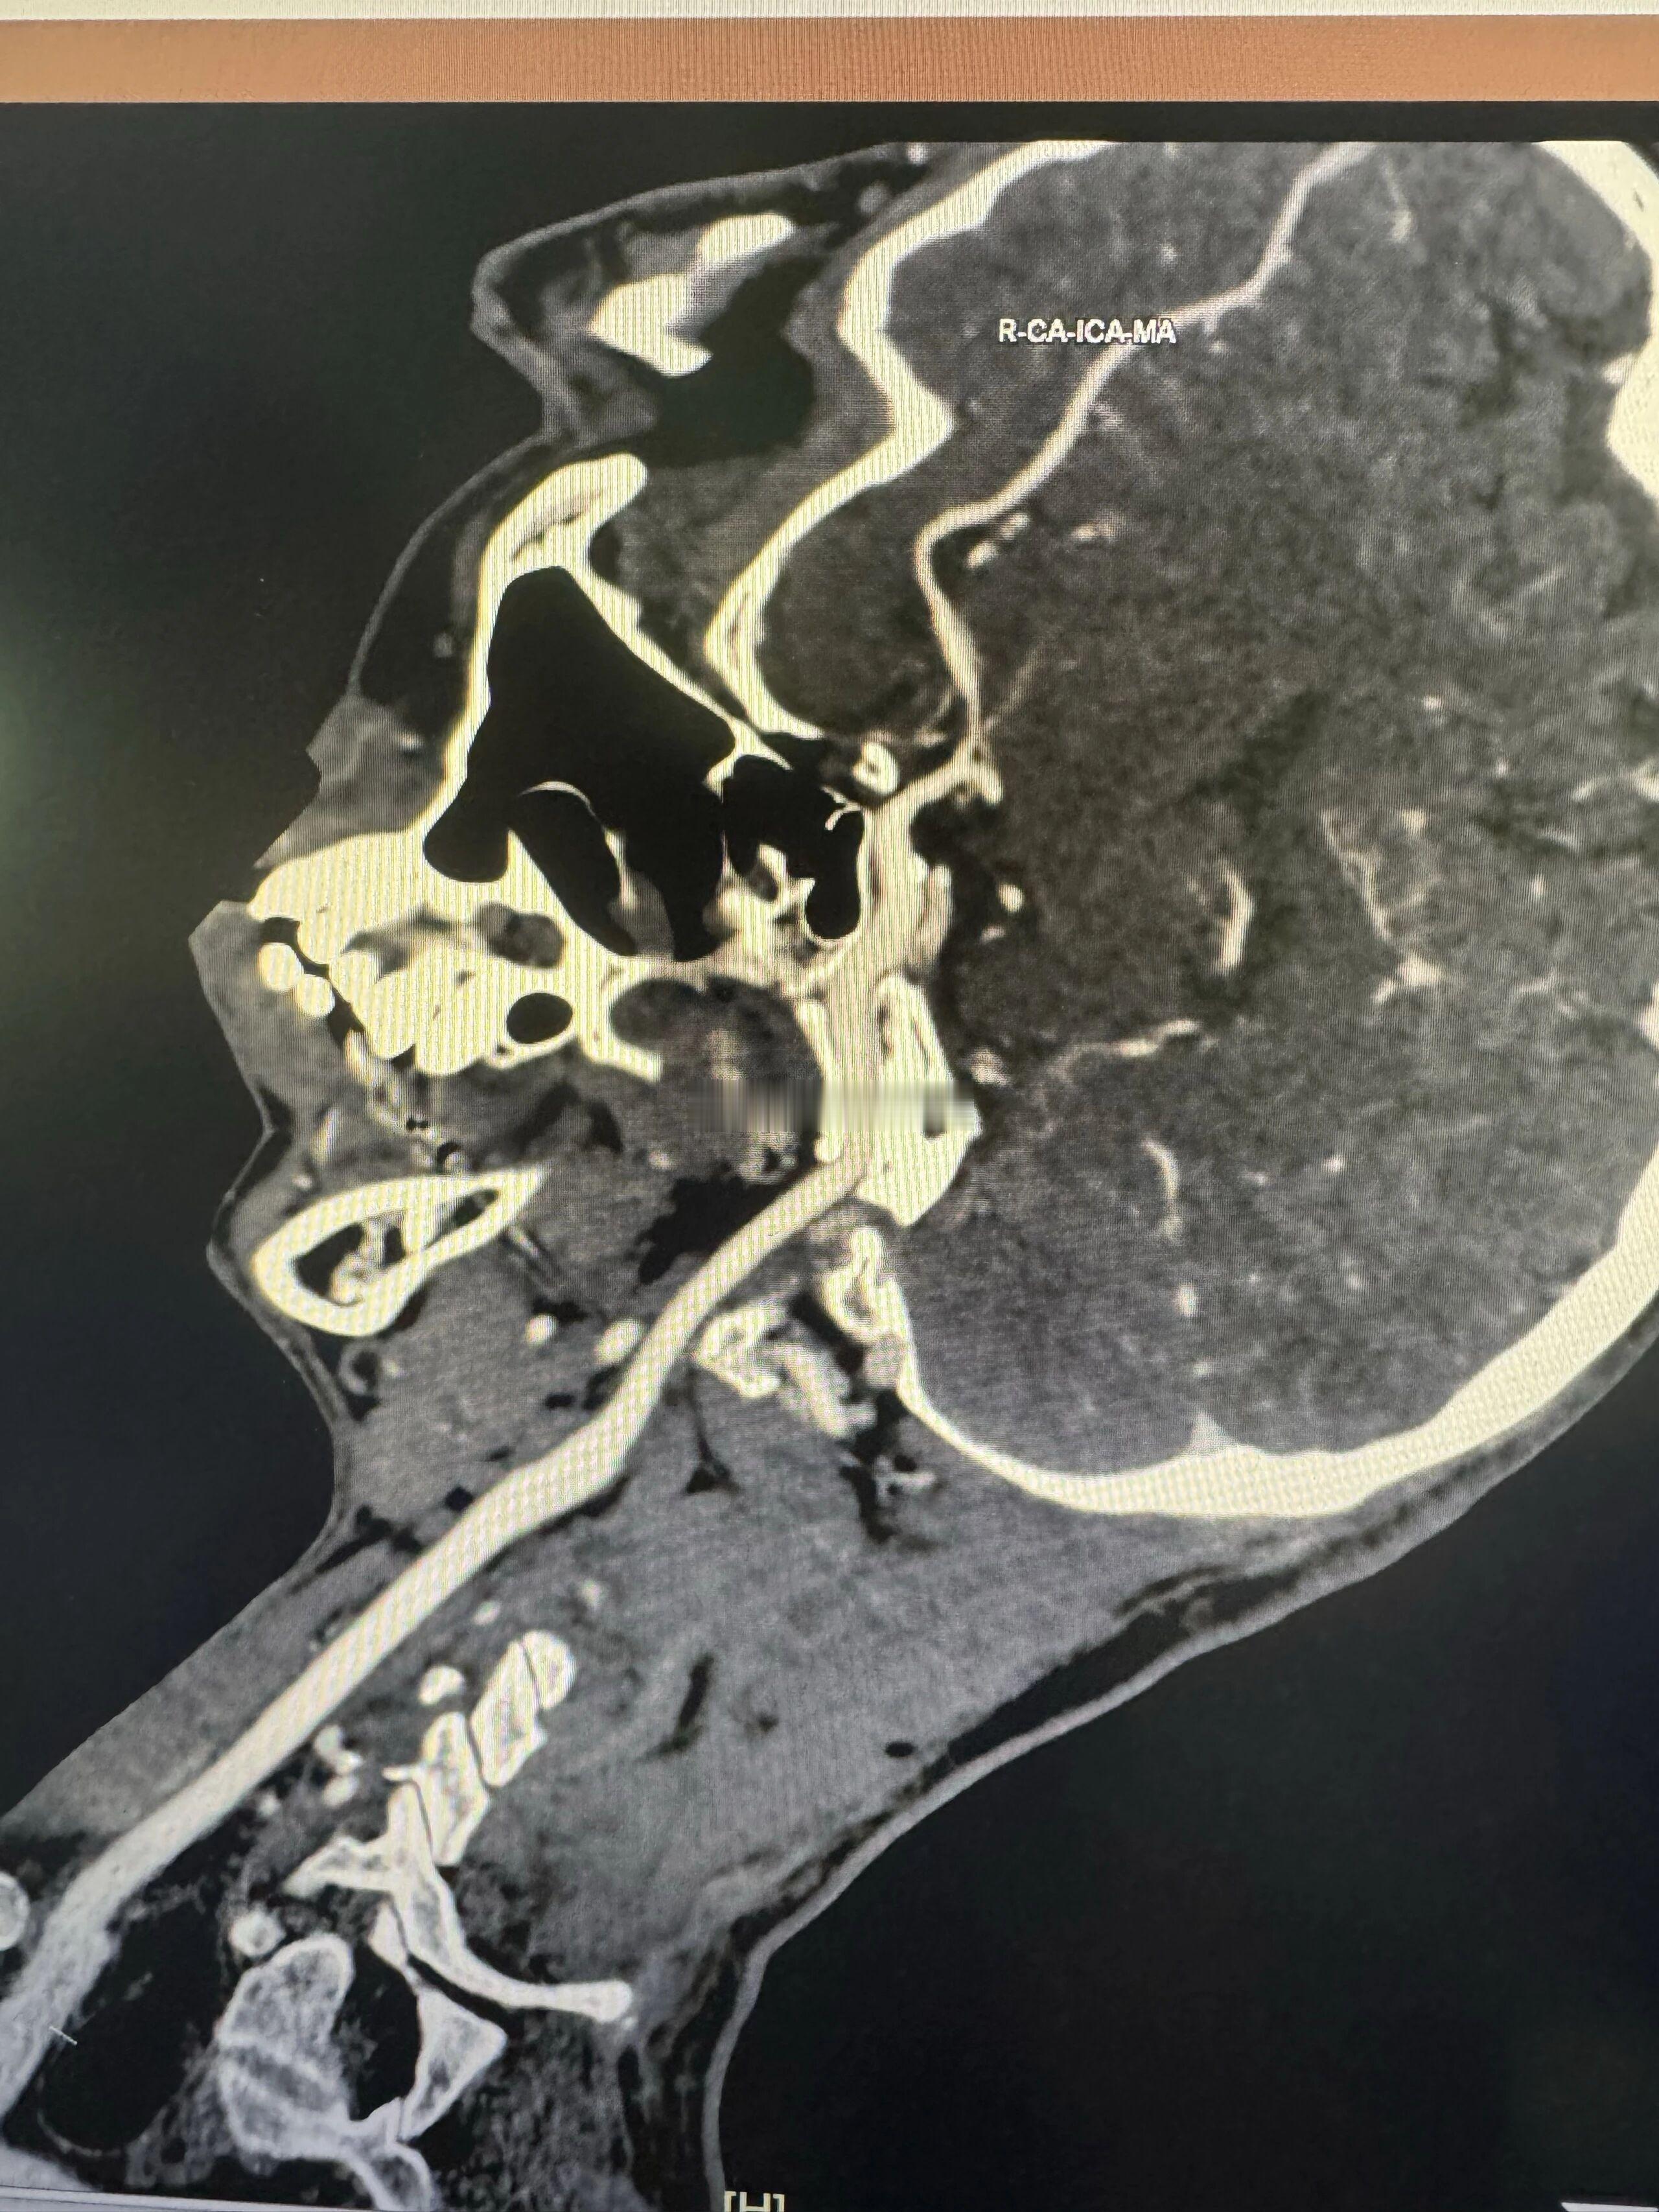

不是裂一道缝,缝上就完事儿。是里外的结构性(骨架)改变,需要多次正畸、矫正手术,一般达不到完美。